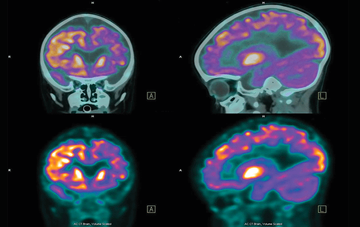

مغز و اعصاب - صفحه 6